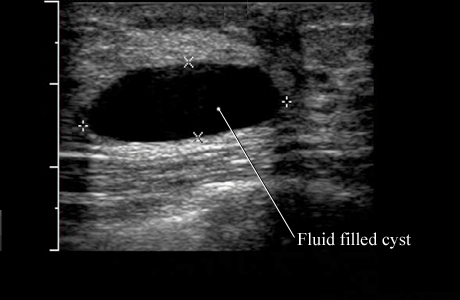

Ultrasound of a Simple Breast Cyst

Image of a simple breast cyst

This ultrasound picture shows a simple cyst with normal breast tissue around it. Because this type of cyst usually does not have any tissue or other particles in it, your doctor knows that it is fluid-filled and can be drained if necessary.